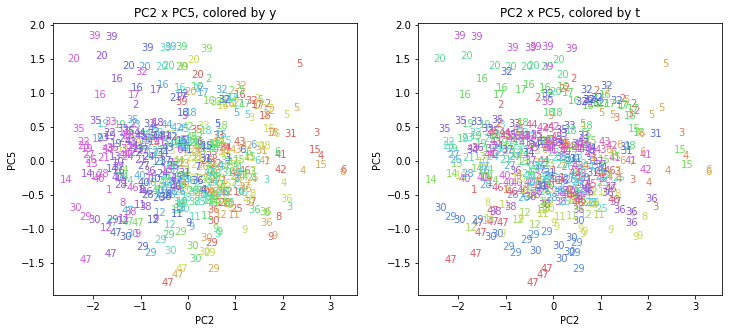

PCAの結果の第n主成分をPCnと表記します。

医療費データの場合と同様に、PCAの結果を見やすく表示するため、seabornのカラーパレットを使って、年月別、都道府県別に色分けして図示してみます(左側が年月別に色分け、右側が都道府県別に色分け)。PC1~PC8まで表示しました。

都道府県番号の表示

上の色分けだけでは都道府県が区別しにくいので、医療費データの場合と同様に、点の代わりに都道府県番号をプロットした図も描いておきます(色分けは上と同じ)。

医療費データの場合ほどはっきりとはしていませんが、PC2が概ね時間の経過を表す成分で、残りの成分が時点によって変わらない地域の特徴を表す成分となっているようです。

また、PC1×PC3を見ると、47沖縄が他の都道府県からかなり離れたところに位置しており、沖縄の地域差が際立っているのが分かります。これは、以前別の記事で年齢階級のない健診データでPCAを実行した場合と似た結果となっています。

今回は、医療費データと同様に、健診データ240次元についてPCAを実行してみました。PCAの結果、医療費データの場合ほどはっきりしとはしていませんが、第2主成分が概ね時間の経過を表す成分で、時間軸に沿った全体的な動き(全国的な動き)を表しており、それ以外の成分が地域の特徴を表す成分で、この10年間あまり変わっていないことがわかりました。